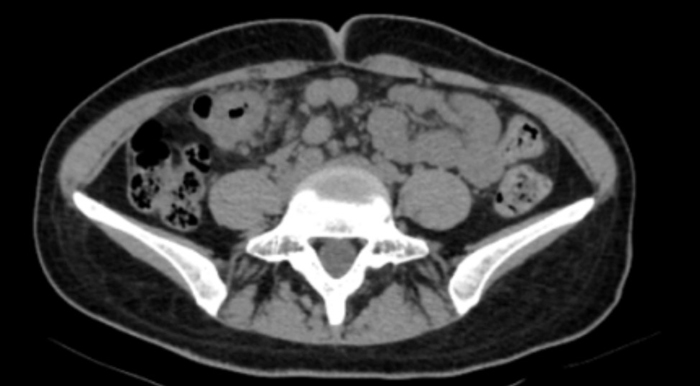

【胸科故事】一根细针揭开纵隔肿物…

一个月前,我收到胸外科同事递来的一张内镜检查申请单:36岁男性,发现“纵隔肿物”。这类患者在我院并不少见,但每一次,我都如履薄冰。打开他的胸部CT,我仔细观察肿物与食管、气管的位置关系——距离够近…